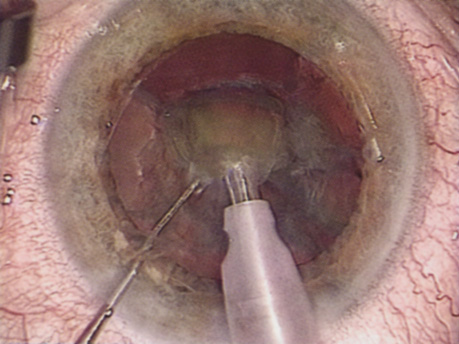

HYDRODISSECTION Hydrodissection can be performed after the surgeon has successfully completed capsulorrhexis.97 If the capsulorrhexis is not intact, fluid forced around the interior of the capsule may cause the bag to splay open. With capsulorrhexis, hydrodissection is a safe and extremely useful maneuver. Hydrodissection can be thought of as two maneuvers: hydrodelineation and cortical cleaving hydrodissection. By placing a 27-gauge cannula on a syringe filled with balanced saline solution (BSS), the surgeon can direct fluid beneath the residual anterior capsular rim to create a cleavage plane. Depending on the direction the fluid wave takes, different lamellae of the cataract will be separated. Hydrodelineation is the term used when the cleavage plane separates the adult nucleus from the fetal nucleus or the adult nucleus from the more peripheral epinucleus. Hydrodelineation often results in the characteristic golden ring sign (Fig. 11). Cortical cleavage occurs when the cortex is separated from the capsular bag (Fig. 12). Finding the cortical cleavage plane may be facilitated by gently lifting the capsular margin away from the cortex with the BSS cannula before injecting. Several small bursts of fluid allow the surgeon to monitor progress of the fluid wave. When dealing with a soft nucleus, the authors strive to perform true cortical cleaving hydrodissection. For a hard nucleus, hydrodelineation allows manipulation of less of the nuclear bulk, although the remaining epinuclear shell must be addressed in an additional step. Hydrodelineation is particularly useful if the nucleus is not freely mobile after cortical cleaving hydrodissection.